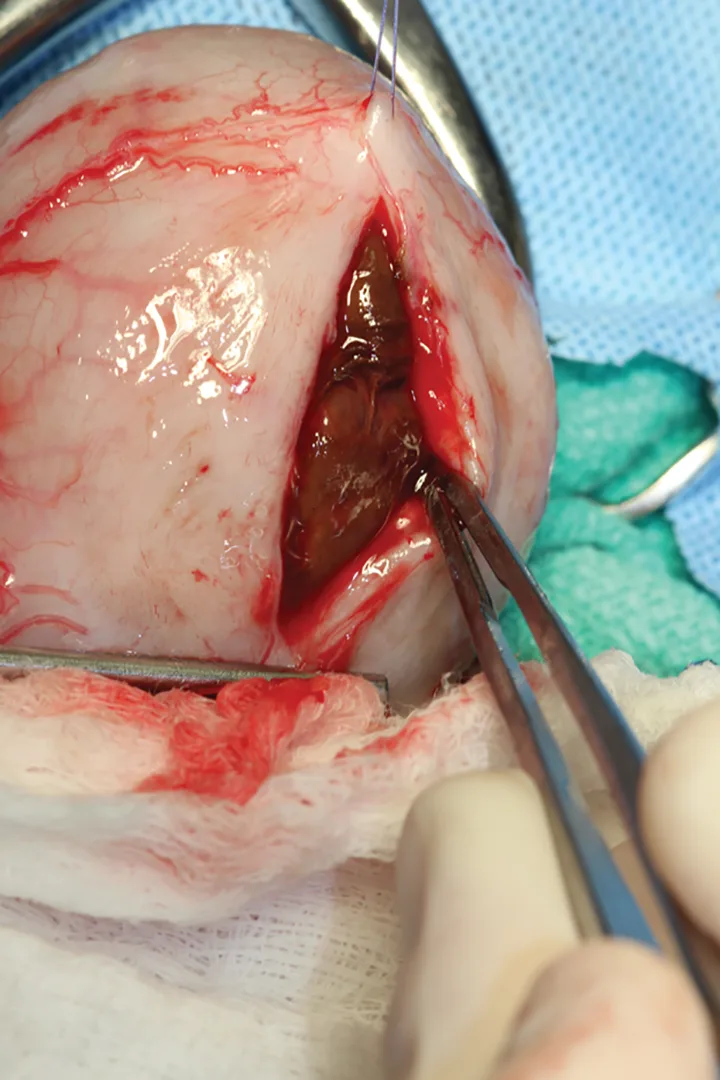

Figure 1. The urinary bladder appears large and there is bilateral renomegaly in this right lateral view; dystrophic mineralization is present in the right kidney.

At initial examination, Ivan was alert and responsive with heart rate, respiratory rate, and temperature within normal limits. He was estimated to be 5% dehydrated and had a large, firm, nonexpressible bladder. He was sedated with 0.015 mg/kg IV of buprenorphine, 0.2 mg/kg IV of midazolam, and administered a total of 2.5 mL of propofol IV for urinary catheter placement. A 5-French red rubber catheter was placed with slight resistance and maintained in place with butterfly tape and stay sutures. A CBC, serum chemistry panel, and plain abdominal radiographs (Figure 1) were performed.

2. Feline idiopathic cystitis is commonly associated with urethral obstruction in male cats.1,3,4 Because this patient had a previous episode of urethral blockage—and because the 2 episodes were close together—perineal urethrostomy was a valid option after correction of azotemia. Plain abdominal films should be taken in feline idiopathic cases to look for cystic or urethral calculi.<sup5sup>